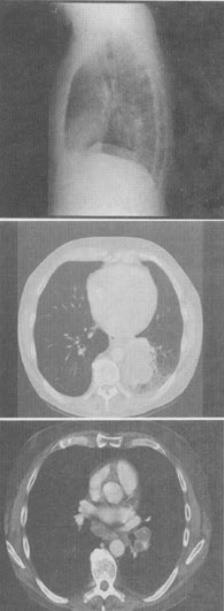

患者60岁,男,体检胸片发现异常,CT检查如图,最可能的诊断是()。

A、肺癌

B、错构瘤

C、肺结核

D、韦格肉芽肿

E、支气管腺瘤

正确答案:

A